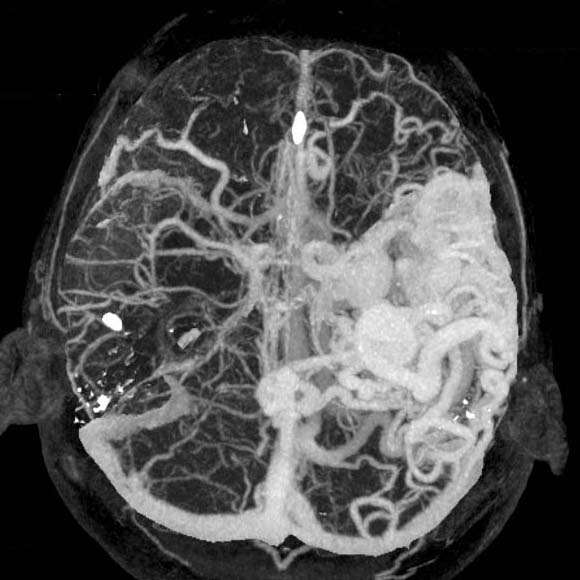

Arteriovenous malformation

0.5mmx4, Pitch 3.5, 200mAs

MIP